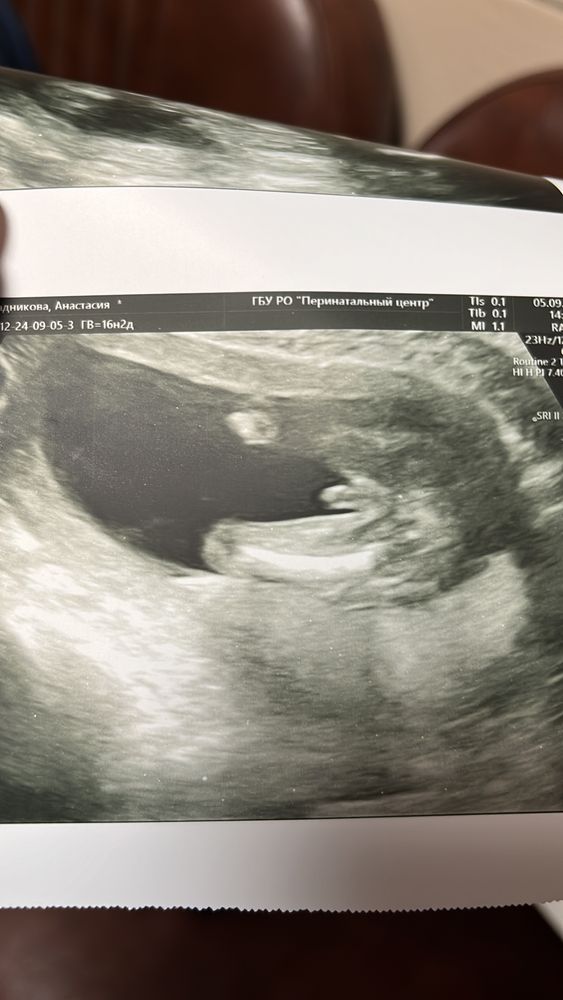

Внеплановое УЗИ)

УЗИ, КТГ, доплерПока ездила в ПЦ по поводу рисков приэклампсии у себя,решила сделать УЗИ ,посмотреть на свою кроху.Теперь могу смело закрашивать кружочек 😄

С сыном все хорошо и это самое главное🙏пусть так и будет дальше❤️🙏